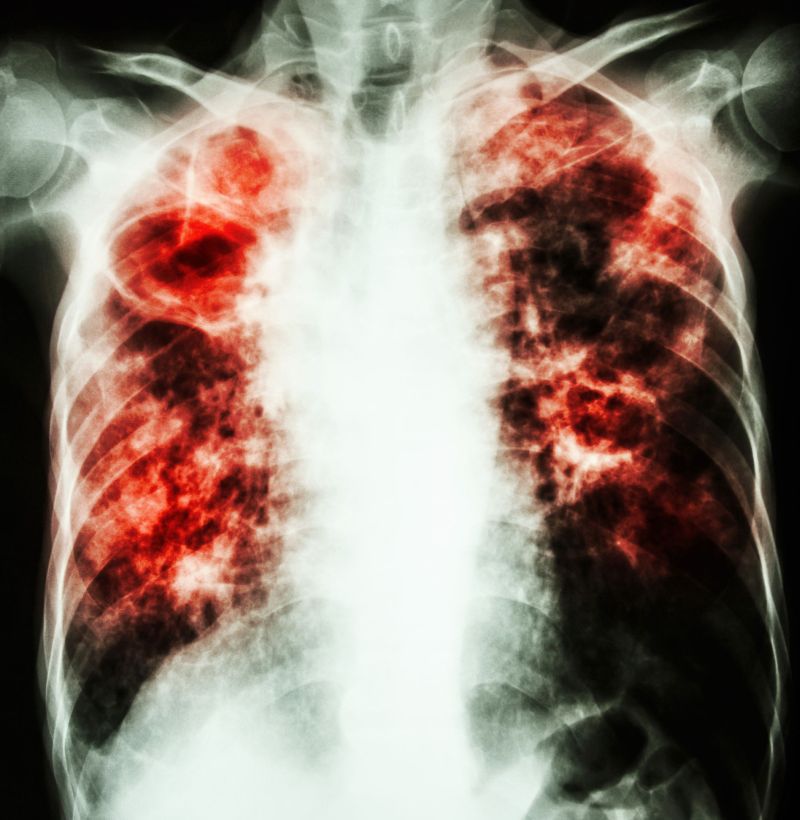

Fibroza pulmonara durata de viata. Fibroza pulmonara defineste cicatrizarea tesuturilor pulmonare. Factori de risc. Implicarea pumonara este progresiva incepand cu bronsite bronsiolite apoi bronsiectazii cord pulmonar si boala pulmonara in stadiu avansat. Numărul pacienţilor români cu fibroză pulmonară idiopatică fpi care se află sub tratament nu depăşeşte 100.

Specialiştii apreciează însă că numărul bolnavilor nediagnosticaţi ajunge la 1000 de persoane. Durata medie de viata pentru oamenii cu fibroza chistica a crescut constant in ultimii 40 de ani. Este un procent destul de mare în condiţiile în care vorbim de metastază pulmonară iar cei mai mulţi bolnavii se află în faze terminale. Fibroza pulmonară este o afecțiune cunoscută și sub denumirea de pneumopatie interstițială difuză fibrozantă caracterizată prin înlocuirea patologică a interstițiului pulmonar cu un țesut conjunctiv sclerozant secundar depunerii la nivel interstițial și alveolar a unor componente celulare inflamatorii fibroza pulmonară este o afecțiune mutilantă care determină în.